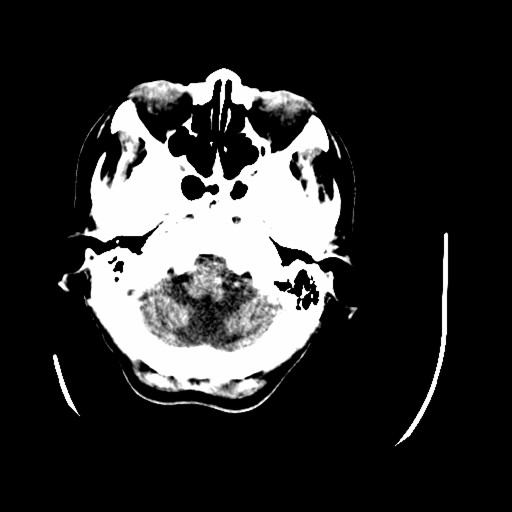

标题: CT16233:女,44岁,智障多年,现感头痛 [打印本页]

标题: CT16233:女,44岁,智障多年,现感头痛

小脑有啥病变?

橄榄桥小脑萎缩.左侧小脑脚腔梗.

为什么不考虑发育畸形呢

1)小脑萎缩。2)小脑蚓部发育不良。

橄榄桥小脑萎缩可能,建议mri进一步检查以进一步排查。

橄榄桥小脑萎缩